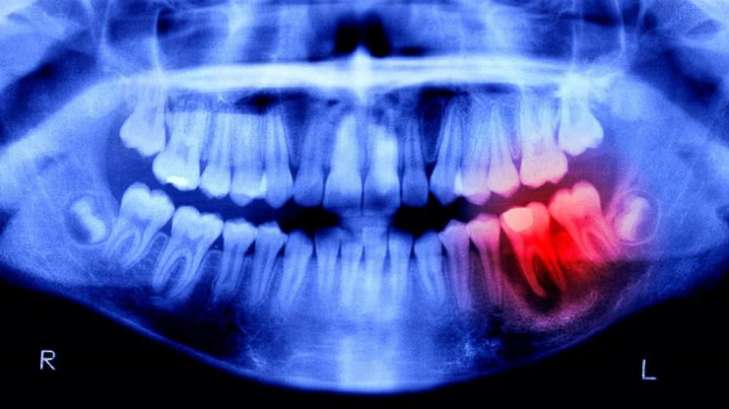

Японські вчені навчилися вирощувати нові зуби

Фото: popularmechanics.com